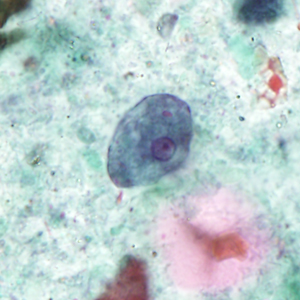

Case #404 – September 2015

A 31-year-old male presented with recurrent anal warts first noticed the summer of 2014. The warts were biopsied and diagnosed as low grade anal intraepithelial neoplasia (AIN1) in March 2015. Other symptoms included mild discomfort with defecation. In September 2015, an anal Pap smear was performed and stained with Papanicolau. Figures A–E show what was observed by the attending pathologist. The objects of interest ranged in size from 7-15 micrometers. What is your diagnosis? Based on what criteria?

Figure A